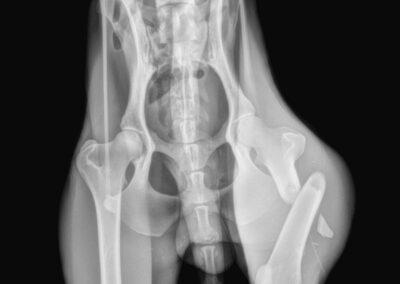

Marcus n’était plus qu’un véritable squelette, avec une fracture complexe du fémur au postérieur gauche. Il a dû vivre un véritable enfer, seul, blessé et affamé…

Il a été opéré en urgence à la clinique du refuge de la FBM, où il est actuellement en convalescence 🩺. La clinique est aujourd’hui totalement saturée, faisant face chaque jour à l’arrivée de nouveaux cas lourds : fractures, blessures graves, chiens brisés par la maltraitance et l’abandon… 😞 Malgré cette situation extrêmement difficile, Marcus a pu être pris en charge et bénéficie désormais de tous les soins nécessaires.